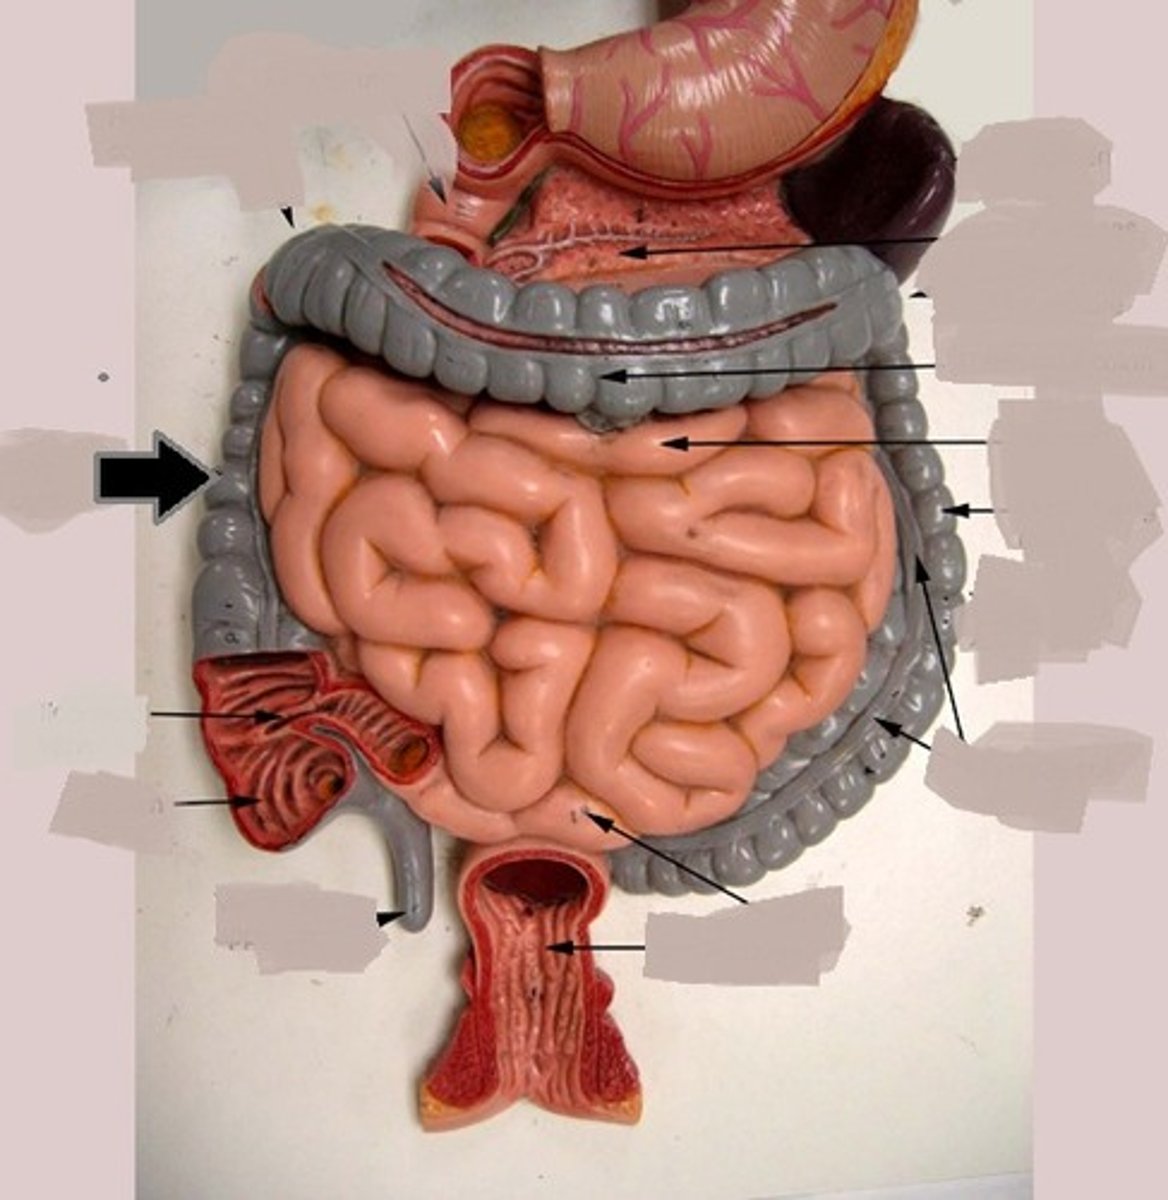

duodenum

duodenum

jejunum

ileum

plicae circulares / circular folds

mesentery

large intestine

cecum

cecum

ascending colon

transverse colon

descending colon

sigmoid colon

illeocecal valve

Apendix

haustrum / haustra

taeniae coli

rectum